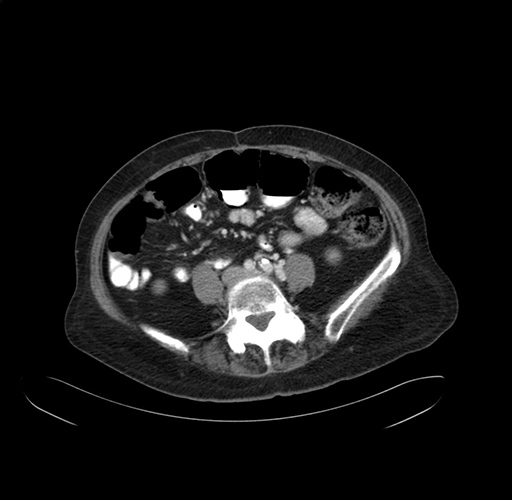

Pre-Chemo: Axial Venous

Axial Venous